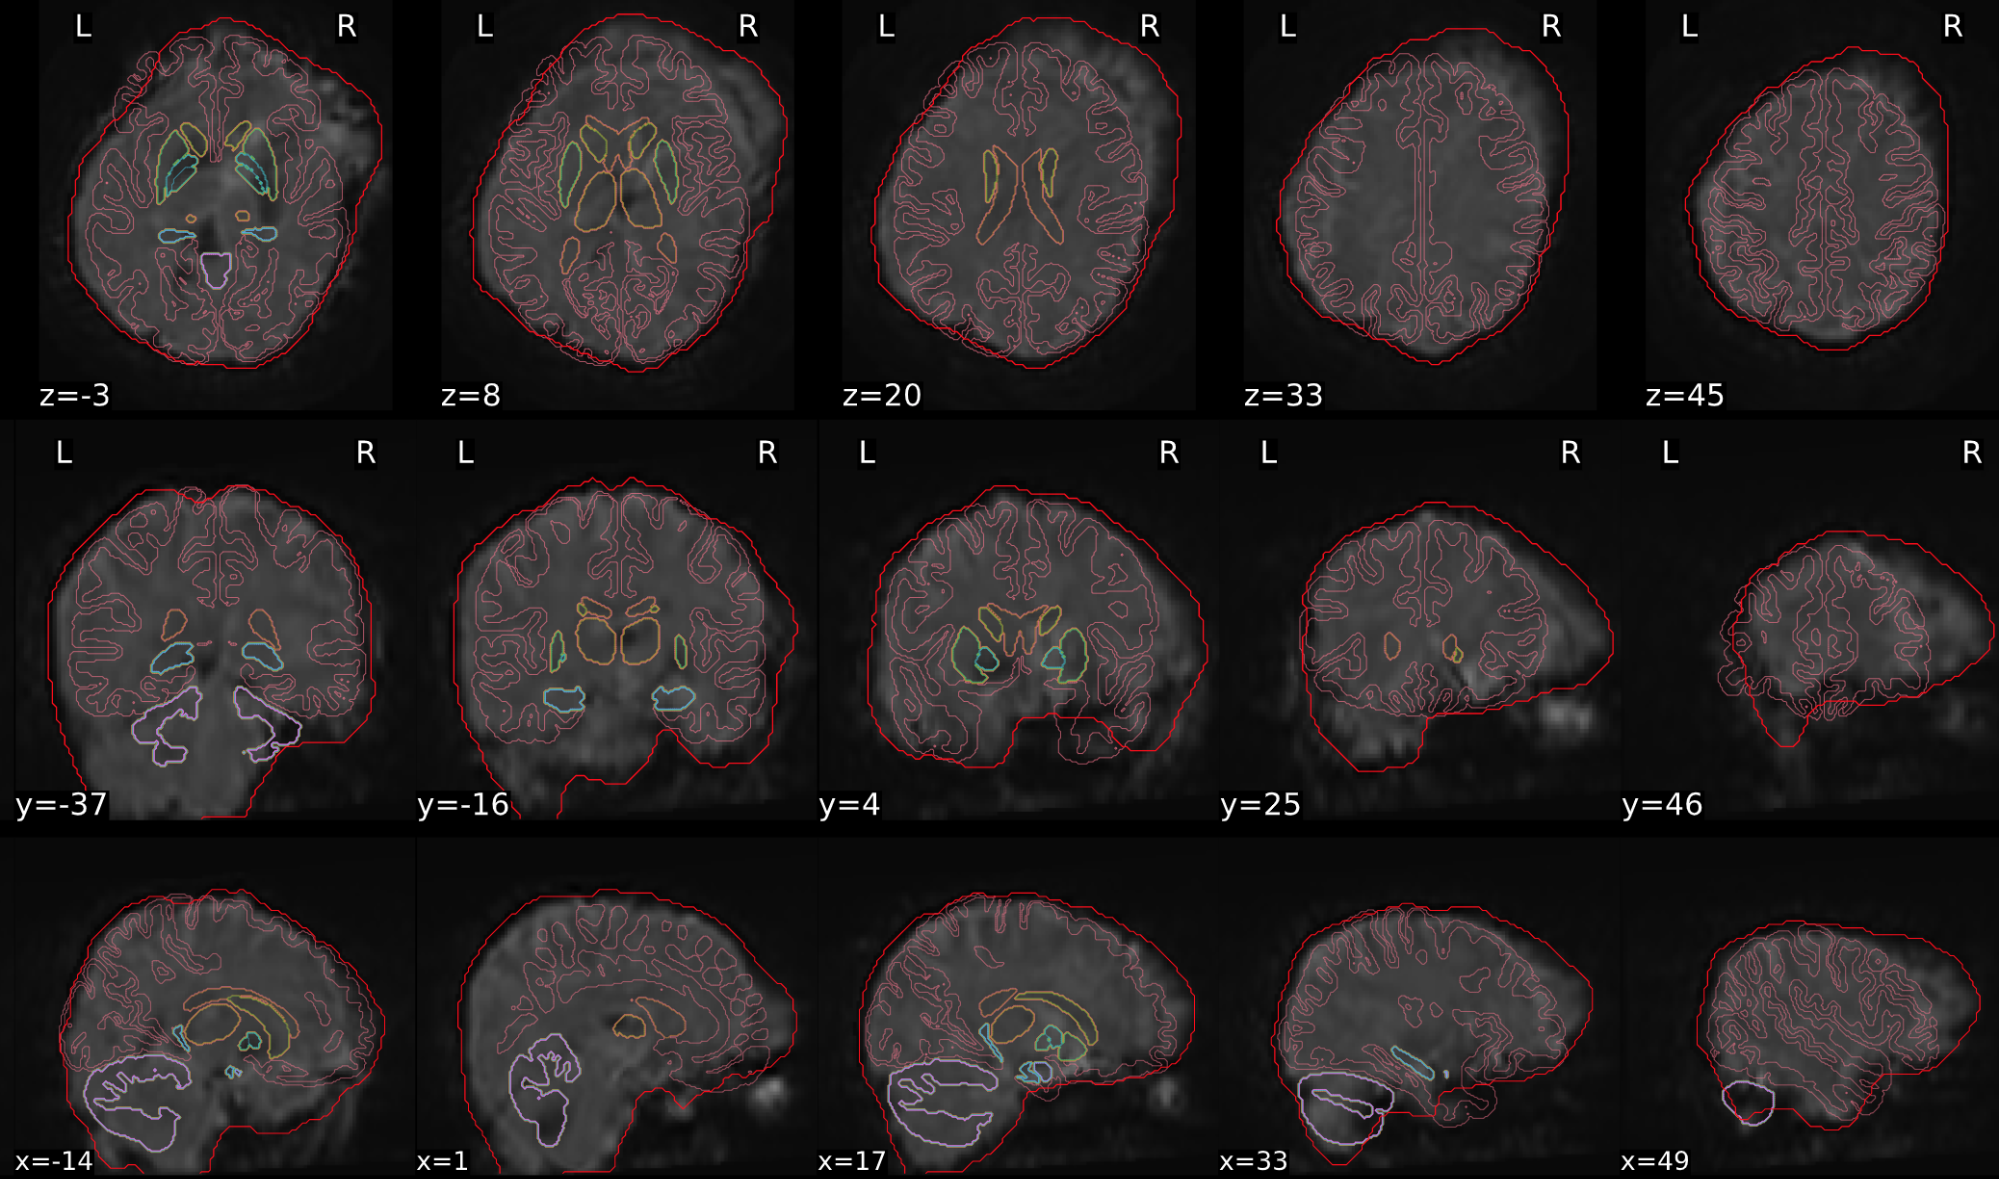

dT1w spatial normalisation

This QC step shows the registration of the T1 image to MNI space.

The registered T1 image is shown in the background with a brain atlas in MNI space as an overlay.

Example of a good subject

- If the registration performed well, you should see an overlap (i.e., correspondence of structures) between the MNI template and the T1 registered to the MNI space.

Example of a bad subject

- In case of poor registration, you should see a misalignment between the MNI template and the T1 (e.g., brain shifted down).

Summary

| good | bad |

|---|---|

| Structures of the MNI template and the registered T1 are well aligned | Structures of the MNI template and the registered T1 aren’t well aligned, e.g. brain is shifted downwards |